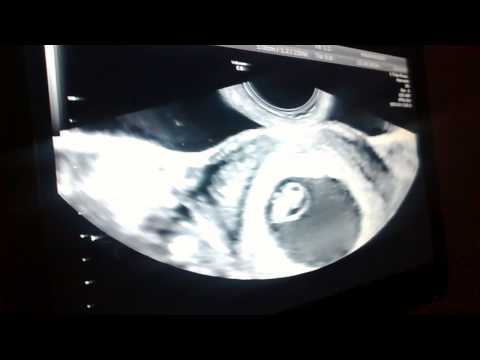

Hoje foi o dia da primeira ultrassom, sou pequenininho do tamanho de um botão, mas ouve meu coraçãozinho como é forte.

A data prevista para o parto bateu com as contas da médica e dos apps. Será 29 de maio de 2015.